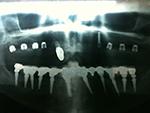

Kurzimplantate und Sofort – Implantate: